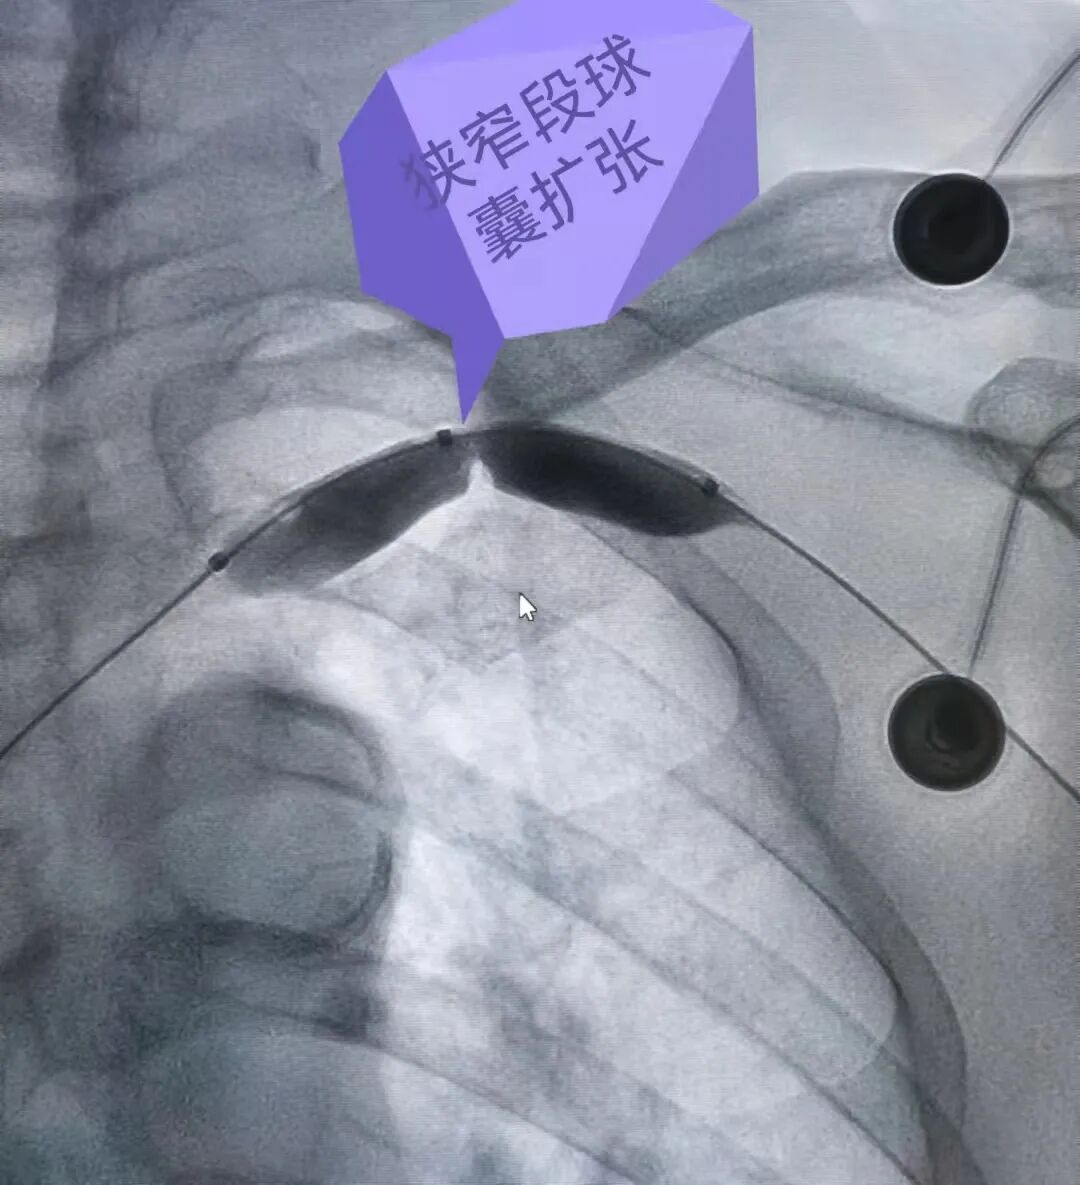

下面由我们介入中心的杨帆主任快问快答给大家做个简单的科普吧! 问:杨主任,只是做个透析嘛,怎么会手肿胀呢? 杨主任:球囊扩张是肿胀手的首选,不需要放支架,因为支架置入易使远期并发症明显增加。那么,哪些情况应该植入支架呢?我们可以根据球囊扩张后复发的时间来确定,通常采用3个月为期限,如果三个月内复发,可以植入支架,否则,应该行重复性球囊扩张,每3-4个月扩一次,我们将这种方式叫“维护性球囊扩张”。